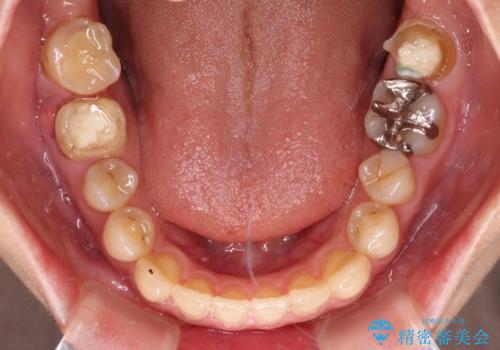

- 上下前歯の開咬とデコボコを気にして来院された患者様です。

開咬(オープンバイト)はインビザラインによる矯正治療がワイヤー装置と比べて圧倒的に有利であるため、インビザラインによる矯正治療を行うこととしました。

通院されなかった時期があって治療期間が長くなったり、奥歯に抜歯が必要な歯があったりと、治療は一筋縄にはいきませんでしたが、何とか治療を終えることができました。

今後はインプラント治療やむし歯治療を進めて行く予定です。